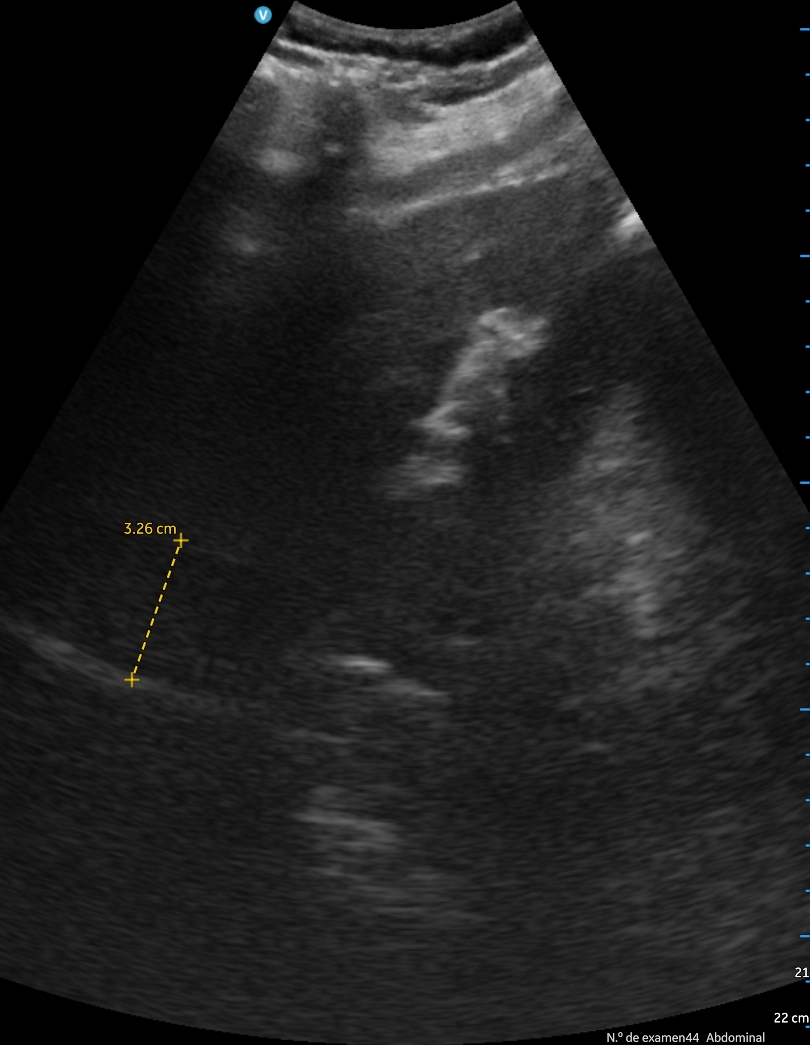

Se aprecia atelectasia lobar media con derrame pleural derecho de unos 150 cc, signo de la medusa. Líneas B en patrón B3 en ambas bases. Cavidades cardiacas normales con correcto funcionamiento valvular, adecuada contractilidad sin indicios de derrame pericárdico. Aumento de vena cava de 2,57 cm no colapsable.

A los 2 días, el paciente presenta empeoramiento de clínica, con disminución SpO2 a 90%, persistencia de fóvea intensa y disnea de reposo. Se revalora ecográficamente encontrando aumento de derrame pleural, ahora 500 cc, una vena cava de 3,27 cm no colapsable y derrame pericárdico. Finalmente se decide derivación hospitalaria.